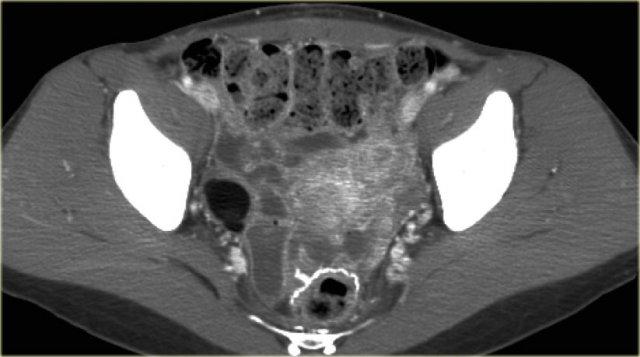

Trường hợp tiếp theo là siêu âm qua thành bụng cho thấy một khối nang đa thùy bên trái.

Hình ảnh này gợi ý u nang tân sinh buồng trứng nhưng không xác định được buồng trứng.

CT trên cùng bệnh nhân cho thấy một khối nang đa thùy tiếp giáp bàng quang, có liên quan đến tĩnh mạch buồng trứng trái (mũi tên).

Có các vách ngăn dày và thành dày không đều.

Dựa trên hình ảnh CT này, không thể phân biệt giữa tổn thương buồng trứng lành tính như u nang tuyến xơ và tổn thương buồng trứng ác tính.

Tổn thương được phẫu thuật cắt bỏ và kết quả giải phẫu bệnh xác định là u nang tuyến xơ.